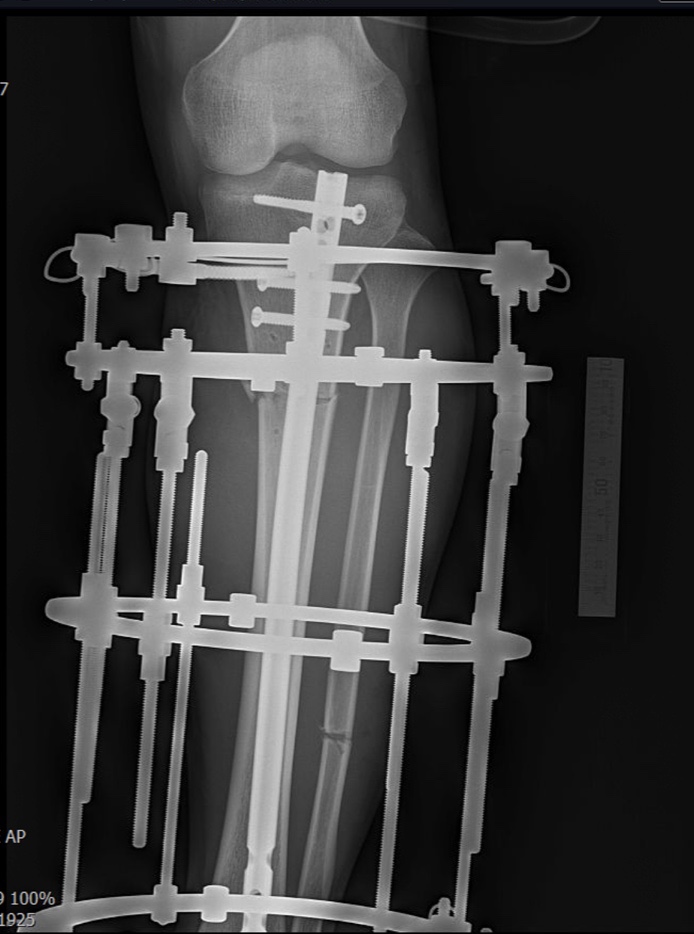

오늘 키 수술 재활, 소요시간에 대해서 글을 써 올려드렸었는데 이 부분에 대해서 할 이야기가 많고 환자분들이 가장 궁금해하시는 부분이라 종아리 속성연장수술을 받게 되면 얼마큼의 시간이 필요한지 한번 알려드려보고자 합니다.

일상 복귀: 목발을 2-3주 사용 가능하며, 환자분에게 남아있는 불편감은 있으나, 회사를 다니거나 학교를 다니는데 큰 지장이 없는 상태로 정해봅니다. 걷거나 할 때 까치발이 남아 있거나 발목과 무릎에 통증이 약간씩 남아 있는 경우가 있을 수 있지만, 주변 사람들은 느낄 수 없는 정도일 때 직장과 학교생활이 가능하다고 할 때, 그 시기까지 종아리 속성연장 후 필요한 시간을 정리해보면

일단 먼저 설명드려야 되는 부분이, 5-6-7-8센티는 필요한 기간이 아주 정비례로 늘어나는 것이 아닙니다. 연장 목표가 일정 부분 이상 올라가게 되면, 더 많은 소요기간이 필요하게 됩니다. 1센티 연장에 1달의 시간이 필요하다고 아주 대략적으로 그리고 약간 여유 있게 계산해볼 수 있는데요, 6센티를 연장하고 일상생활로 돌아가는데 6개월의 계산이 나오지만 사실상 5개월정도의 시간이면 일상생활을 시작하게 되고, 4개월반정도 필요한 경우도 있습니다.

그런데 만약 환자가 5센티만 연장을 원해서 5센티 연장을 했다면, 한달의 기간이 줄어드는 것이 아니라 1달 이상의 필요한 기간이 줄어들게 됩니다. 5센티 연장은 대략 2개월이 소요되고, 뼈 형성이 완성되는데 필요한 기간이 1.5개월에서 넉넉히 2개월이라고 잡아도 4개월이 되는데요 그렇다면 경과가 좋은 환자들인 경우 3.5개월 정도면 목발을 사용하거나 잠시 사용기간을 거치면서 일상생활로 돌아가기도 합니다.

반대로 7센티, 8센티로 연장 길이가 환자의 연부 조직이 견딜 수 있는 범위를 많이 벗어나게 될수록 뼈 형성의 능력, 환자가 가지고 있는 고유의 특징의 한계를 벗어나려 할수록 회복기간은 계산된 기간보다 더 길어질 수 있습니다.